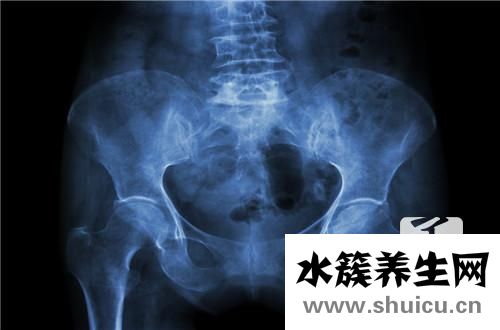

盆腔積液為女士骨盆中的液體,其在臨床醫(yī)學(xué)上被分成生理性的與生理性的兩類。生理性的盆腔積液是女性身體一切正常狀況,大部分女士都多多少少的存有生理性盆腔積液。此外,女性檢查的時(shí)間針對(duì)盆腔積液的查驗(yàn)結(jié)果也是有所區(qū)別的。因此,若是查驗(yàn)結(jié)果超出了10公分這一定義指標(biāo)值,女士可選別的時(shí)間再開(kāi)展一次查驗(yàn)。

而若是查驗(yàn)結(jié)果顯著超過(guò)10公分,那麼基本上能夠分辨當(dāng)今人體內(nèi)存有的盆腔積液為生理性的。醫(yī)師強(qiáng)調(diào),生理性的盆腔積液不是需要醫(yī)治的。可是,生理性的盆腔積液則需要醫(yī)治。生理性的盆腔積液多是由于發(fā)炎問(wèn)題來(lái)講引起的,因此醫(yī)治上關(guān)鍵選用消炎方式 。

那麼,盆腔積液打消炎藥可以嗎?自然是能夠的,消炎藥具有的消炎的功效是能夠用以醫(yī)治女士生理性盆腔炎的。該治療方法歸屬于西醫(yī)方面醫(yī)治范疇,一些女士針對(duì)這一治療方法存有顧慮的原因關(guān)鍵取決于,擔(dān)憂癥狀的醫(yī)治會(huì)對(duì)人體產(chǎn)生負(fù)面信息影響。關(guān)鍵是由于,一些治療盆腔炎的藥品歸屬于抗生素,長(zhǎng)期服用針對(duì)人體的確會(huì)產(chǎn)生負(fù)面信息影響。因此,最后怎樣開(kāi)展醫(yī)治,應(yīng)參照醫(yī)師的建議來(lái)開(kāi)展。